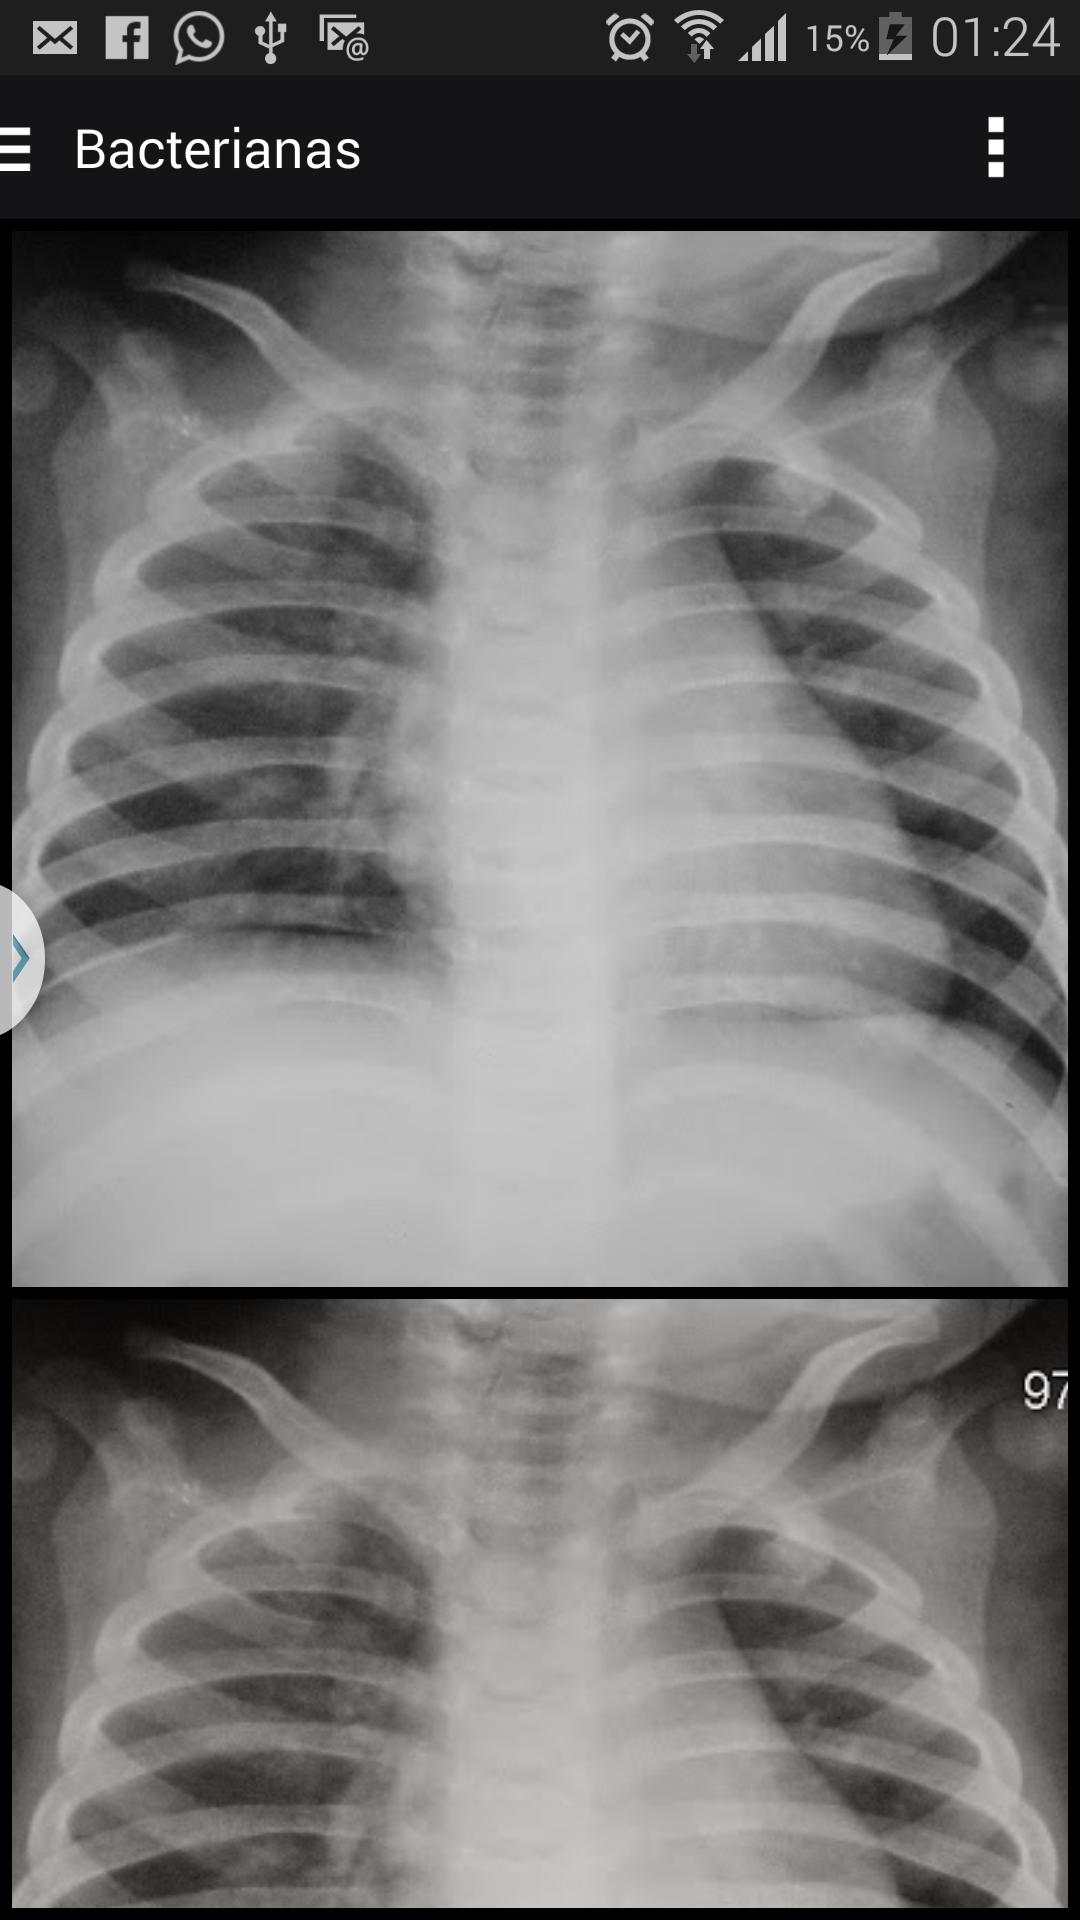

X射线图像支持儿童肺炎的诊断

世界卫生组织(WHO)将胸部X射线视为目前可用于诊断日常临床实践的最佳方法。但是,对异际变异的研究在医学的所有领域都很常见,但是在图像研究中占主导地位,鉴于在这一领域,观察者的表现代表了过去十年中获得的脆弱部分,与技术进步形成鲜明对比。

黄金”的诊断测试评估的基本因素。在胸部的射线照相诊断的情况下,尤其是在儿童时期,图像解释的准确性是通过间和观察中的一致性来主观评估的,因为很少有一种模式可以用作肺炎诊断的参考(标准)。